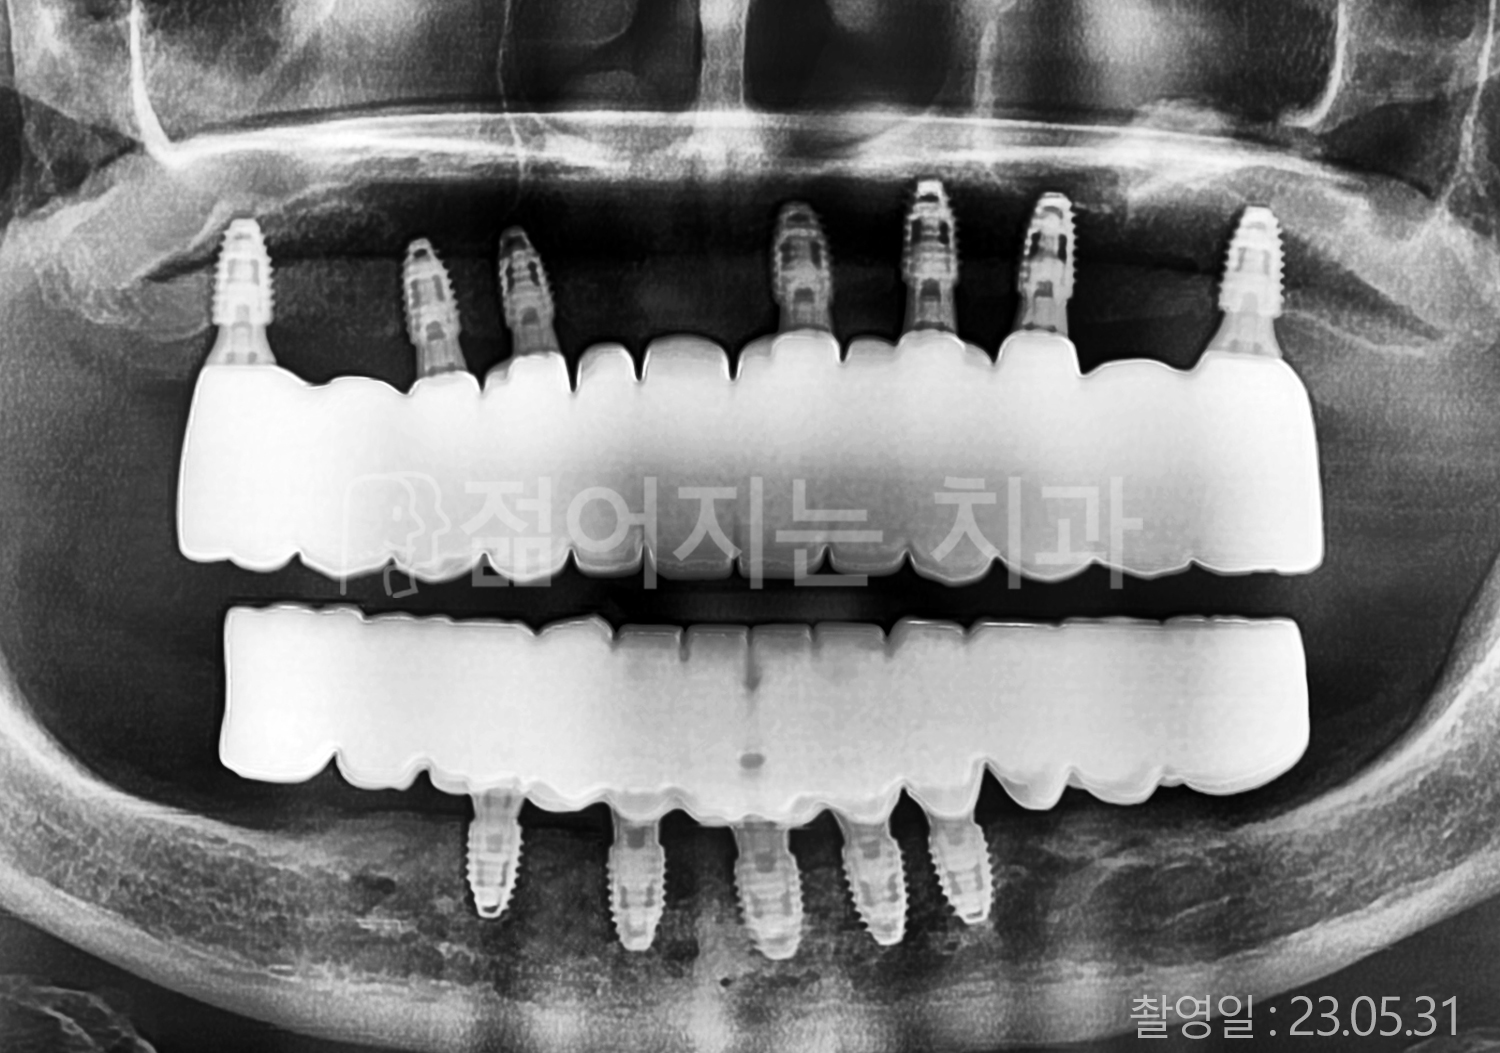

• 40대 전체치아 10개 이상 임플란트

• 50대 전체치아 10개 이상 임플란트